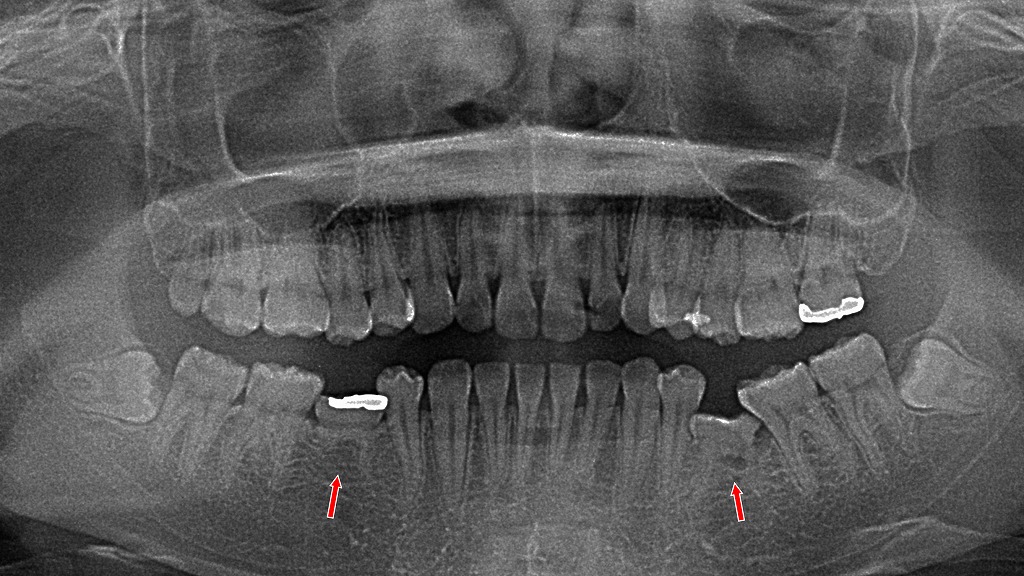

- 7.4. 🔍 左右の下あごに乳歯が残存 第二小臼歯の先天欠損症例

- 7.4.1. ① 両側の下顎:第二乳臼歯の残存(矢印付近)

- 7.4.2. ② 第二小臼歯の先天欠損

- 7.4.3. ③ 咬合や将来への影響

🔍 左右の下あごに乳歯が残存 第二小臼歯の先天欠損症例

このパノラマレントゲンでは 左右の下顎に第二乳臼歯が残存 しており、本来生えてくるはずの 第二小臼歯(永久歯)が先天的に欠損 している状態が確認できます。

① 両側の下顎:第二乳臼歯の残存(矢印付近)

- 赤い矢印で示されている位置に 乳歯(第二乳臼歯)が残ったまま になっています。

- 通常、第二乳臼歯は12歳前後で抜け、下から第二小臼歯が生えてきます。

- 本症例では、その 永久歯の芽(歯胚)が存在せず、乳歯が自然脱落しない状態 です。

- 乳歯の根はやや短く、加齢とともに吸収していく可能性がありますが、現在は保持されています。

② 第二小臼歯の先天欠損

- 下顎の左右とも、第二小臼歯の歯胚がレントゲン上に確認できません。

- 先天欠損は比較的よく見られる歯の発育異常で、第二小臼歯はその代表的な部位です。

- 永久歯が無いことで、乳歯が長期的に機能しているケースもあります。

③ 咬合や将来への影響

- 乳歯は永久歯よりも寿命が短く、将来的に

- すり減り

- 破折(割れ)

- 歯根吸収による動揺

が起こる可能性があります。

- その際は、

- インプラント

- ブリッジ

- 矯正治療を含めたスペースクローズ

などが選択肢になります。

📝 まとめ

「左右の下の奥歯(乳歯)がまだ残っていますが、これは生まれつき後継の永久歯が無い“先天欠損”によるものです。現時点では乳歯がしっかりしているため、そのまま使えますが、将来的に弱ってきた場合は治療方法を一緒に検討していきます。」